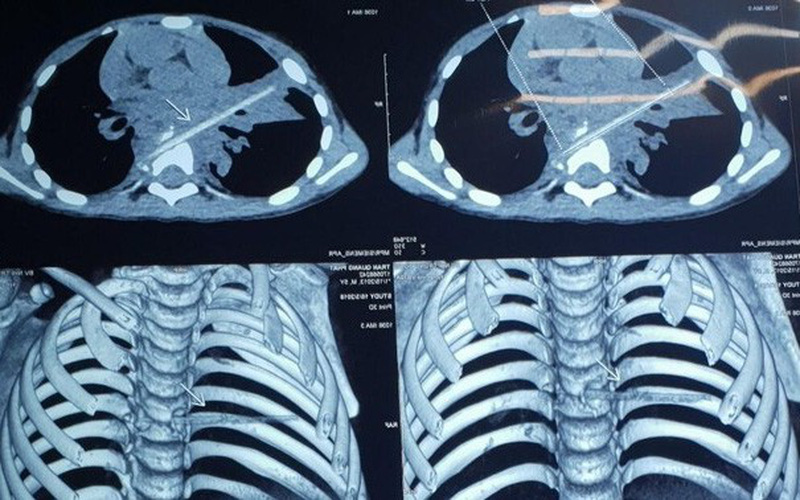

Hình chụp cho thấy dị vật trong phổi bệnh nhi.

Hình ảnh chụp vi tính cắt lớp sau đó cho thấy bệnh nhi có một dị vật dài nhọn kích thước 72x4 (mm) tại vị trí nhu mô thùy phổi ở thùy giữa phổi phải.

Dị vật này đi từ trước ra sau, xuyên qua khe giữa 2 thân đốt sống 6,7 và làm vỡ thân đốt sống. Khi nằm lại trong cơ thể, dị vật gây phản ứng thâm nhiễm viêm trung thất sau quanh đốt sống 6,7. Đây cũng chính là nguyên nhân khiến bé Minh phải vào viện vì viêm phổi trong suốt 8 tháng.